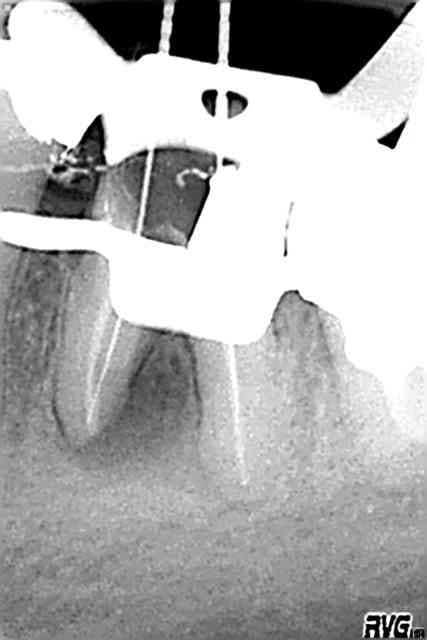

empreinte inlay core + couronne